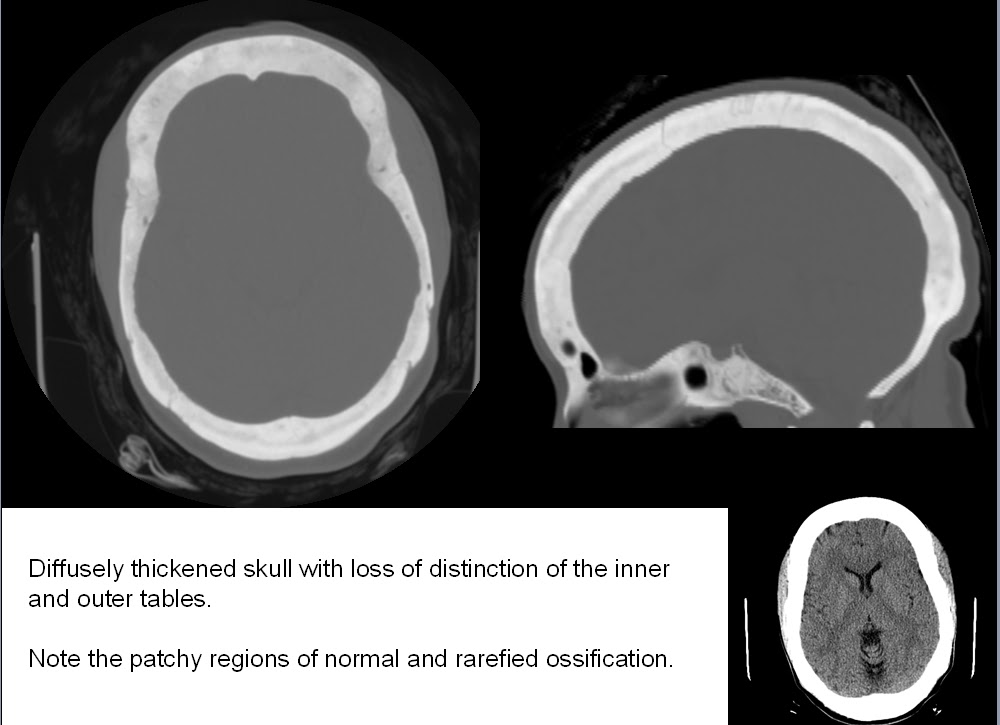

Skull and Spine Renal osteodystrophy and diffuse skull thickening Salt And Pepper Calvarium Radiology Five different infiltration patterns have been described on mri with the “salt. Metabolic bone disease encompasses a diverse group of diseases that diffusely affect. This finding represents tiny spheres of. Calvarial lesions are often asymptomatic and are usually discovered incidentally during computed tomography or magnetic resonance imaging of. Salt And Pepper Calvarium Radiology.

Salt And Pepper Calvarium Radiology . Metabolic bone disease encompasses a diverse group of diseases that diffusely affect. This finding represents tiny spheres of. Calvarial lesions are often asymptomatic and are usually discovered incidentally during computed tomography or magnetic resonance imaging of. Five different infiltration patterns have been described on mri with the “salt.

Calvarial lesions are often asymptomatic and are usually discovered incidentally during computed tomography or magnetic resonance imaging of. Five different infiltration patterns have been described on mri with the “salt. This finding represents tiny spheres of. Metabolic bone disease encompasses a diverse group of diseases that diffusely affect.